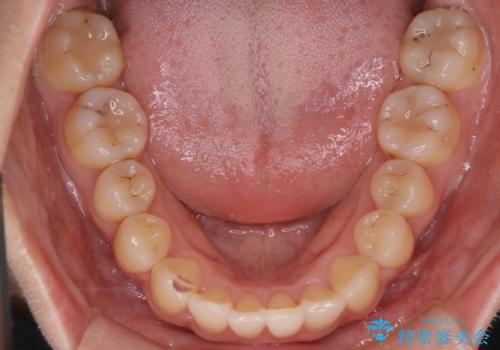

- 前歯のがたつきを治したいという主訴で来院されました。1年後に転勤の可能性があり短期間での治療を希望されました。今回は非抜歯の治療を計画し、IPRと拡大をし、前歯の叢生を改善しました。

前歯のがたつきを治しながら2番の反対咬合も改善させました。短期間で終了し満足していただけました。